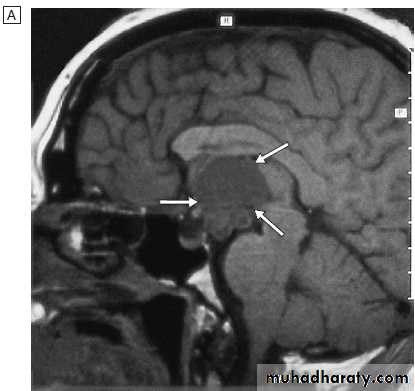

Graves’ disease.

A Bilateral ophthalmopathy in a 42-year-old man. The main symptoms were diplopia in all directions of gaze and reduced visual acuity in the left eye. The periorbital swelling is due to retrobulbar fat prolapsing into the eyelids, and increased interstitial fluid as a result of raised intraorbital pressure.B Transverse CT of the

orbits, showing the enlarged extraocular muscles. This is most obvious at the apex of the left orbit (arrow), where compression of the optic nerve caused reduced visual acuity.